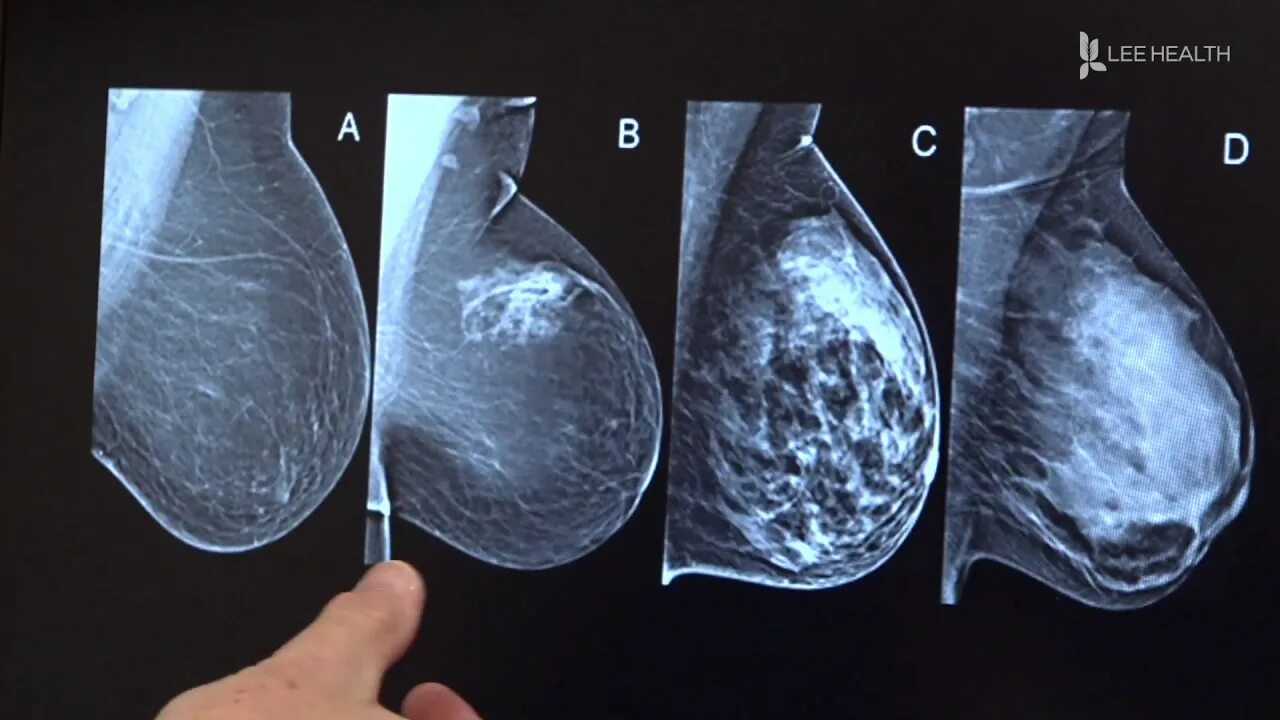

Тип молочных желез acr 2